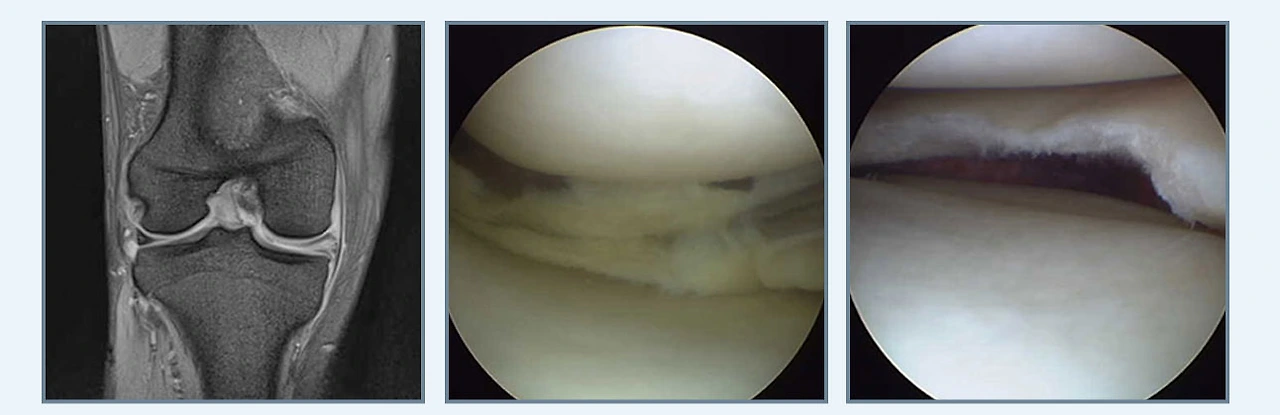

연골판 봉합술

봉합술.PNG

연골판을 봉합해 제 기능을 수행하도록 하는 연골판 봉합술은 크게 후각부 파열과 양동이 손잡이형 파열로 나뉩니다. 연골판의 기능을 보존하기 위해 연골판과 뼈가 부착되어 있는 부분의 가장 후방부인 후각부의 파열을 봉합하는 후각부 파열, 파열부위가 손잡이 젖혀지듯이 움직이기 때문에 관절 사이에 끼어 무릎이 움직이기 힘들어지는 양동이 손잡이형 파열이라고 합니다.

특히 무릎을 구부리는 동작에서 많은 스트레스를 받게 되는 후각부 파열은 생활 습관상 양반다리를 많이 하게 되는 좌식 생활권인 동양권에서 많이 발생합니다. 덧붙여 후각부가 파열되면 연골판의 뿌리가 견고하게 고정되지 않기 때문에 체중이 가해졌을 때 연골판이 고정되지 못하고 밖으로 이탈되는 현상이 발생되어 관절염이 급속하게 진행되기도 한답니다.